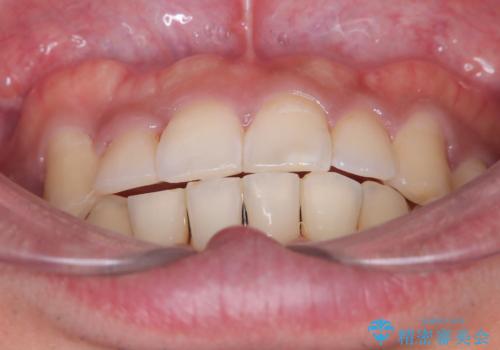

【ワイヤー矯正】八重歯と下の歯の凸凹を治したい

- 主訴:右上の八重歯と、下の歯の凸凹を治したい

上顎右側第一小臼歯と下顎右側第一小臼歯を抜歯しワイヤー矯正を行いました。

右側2級、左側1関係だったため、右側上下第一小臼歯を抜歯し、ワイヤー矯正を行いました。